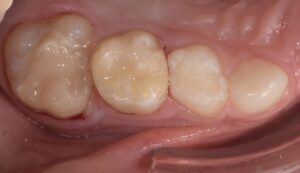

Le congrès de l’EAPD (Académie Européenne d’Odontologie Pédiatrique) a défini des critères de diagnostic en 2003. A savoir des opacités délimités, des fractures post-éruptives, des restaurations atypiques ainsi que que des extractions des molaires. (3) Le diagnostic différentiel doit surtout s’établir entre des amélogénèses imparfaites et des hypominéralisations d’origine traumatique pour les dents antérieures. Cliniquement, les dents vont présenter des colorations blanches ou brunes opaques sur une partie ou sur toute la surface de la dent (Figures 1-2-3-4).

formation dentaire pédodontie Figure 1.

MIH, état des lieux et thérapeutiques Figure 2.

Figures 1-2 : Incisives centrales atteintes de MIH

Figure 3-4 : Molaires atteintes de MIH (HSPM + MIH pour la figure 3)